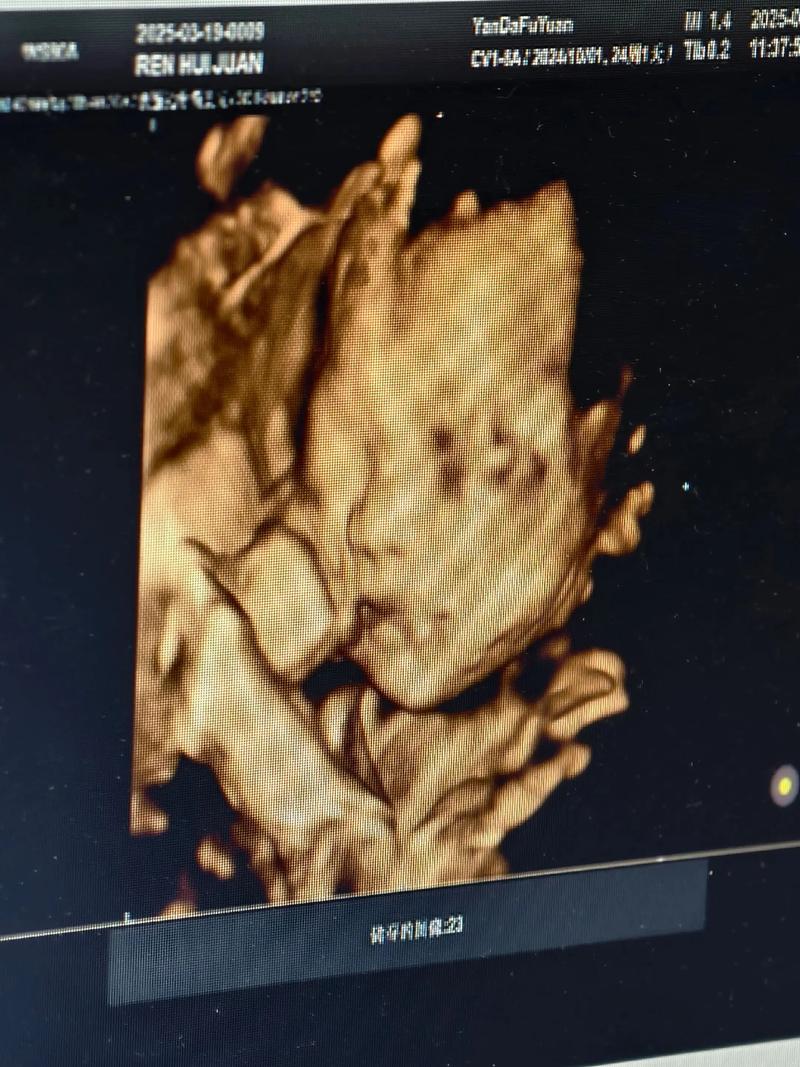

四维成像技术,通常指的是三维成像技术加上时间维度,即可以捕捉到物体在三维空间中的动态变化,在医学、安全监控等领域有着广泛的应用。